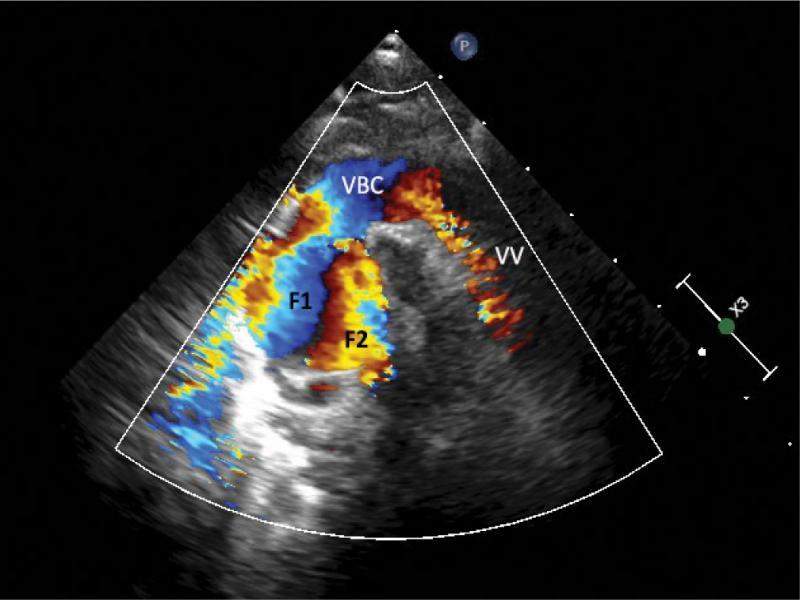

A supracardiac type of total anomalous pulmonary venous drainage (TAPVD) through a 12-millimeter-wide vertical vein with significantly dilated brachiocephalic vein and even more enlarged superior vena cava was diagnosed based on echocardiography (Fig. 1, Fig. 2, Fig. 3, Fig. 4, Fig. 5), and confirmed using CT angiography (Fig. 6, Fig. 7, Fig. 8). A 10 mm secundum atrial septal defect permitted a relatively unrestricted right-to-left atrial flow, and thus the survival of the patient. The right atrium and right ventricle were also enlarged. Echocardiographic signs of pulmonary hypertension were present. The marked dilatation of the SVC and unusual, turbulent flow pattern within this vessel, which was detected on ECHO, suggested that the right upper pulmonary vein drained separately to the SVC. This suspicion was not confirmed by either CT angiography or direct surgical inspection.

Slight anterior tilt of the probe revealed a wide, left-sided vertical vein (VV) – a connection of the pulmonary confluence and systemic veins. The SVC seems wider in this view compared to the former figure, also the upwardly directed flow appears clearer (F2)